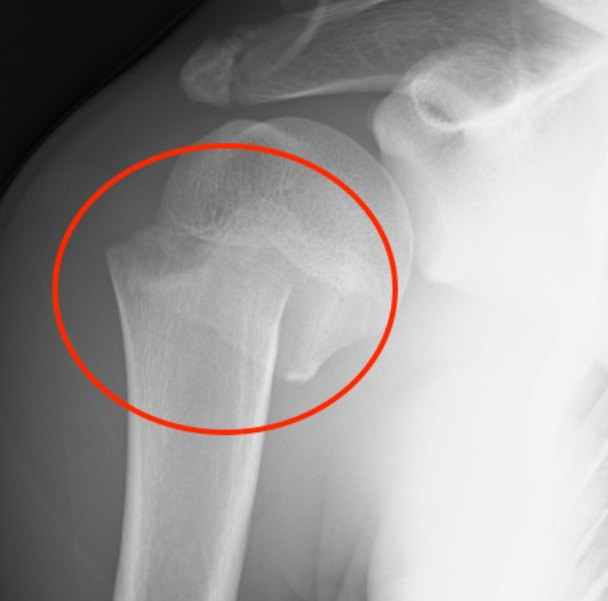

COMPLETE A IMAGEM

1. Corpo da escápula 2. glenoide 3. coracoide 4. colo anatomico do umero 5. tuberosidade maior 6. tuberosidade menor 7. colo cirúrgico

69

8. Espinha da escápula 9. clavícula 10. Art. acomioclavicular 11. Acromio 12. Diafise do úmero